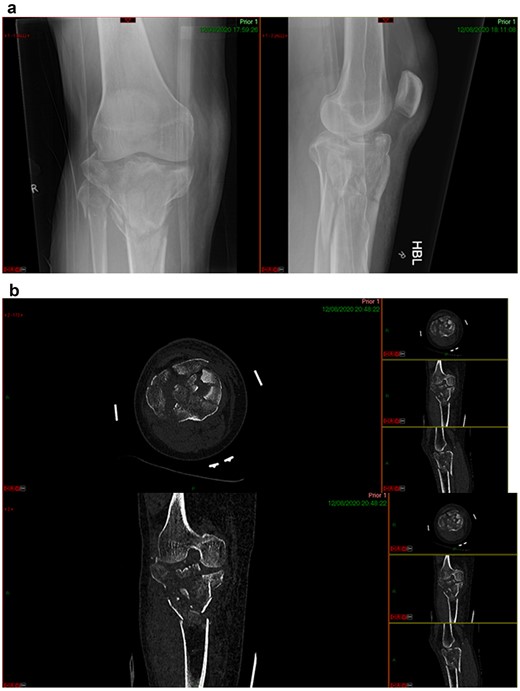

This case report follows a 67-year-old gentleman who sustained a Schatzker VI fracture of his right tibia after falling 2 m from a ladder (Fig. 6). The injury was closed and neurovascularly intact; he was managed initially in a neighbouring health board with a bridging external fixator because of the high degree of comminution. He was referred to the current institution; and at a routine review 3 weeks post-injury, it was noted that a pin had fractured. The external fixator was removed, and he was converted into an above knee cast. He progressed to a Sarmiento cast and then a range of motion brace at 12 weeks. Partial weight bearing was permitted, and he received physiotherapy. He was kept under regular review and the fracture had united (Fig. 7); he was noted to have a range of movement of 10°–60° with healed pin site wounds. At 8 months post-injury, he underwent total knee arthroplasty utilizing a posterior stabilised Depuy Synthes (Warsaw, In) Attune revision tibial metaphyseal sleeve and stem, and femoral component without sleeve or stem. The patient had an uncomplicated recovery and kept under routine review in the outpatient clinic. At 6 months’ review, the patient had a range of motion of 0°–105°, fully healed wound and reported a significant improvement in pain. The patient used no walking aids, and the Oxford Knee score was 40 (Fig. 8).